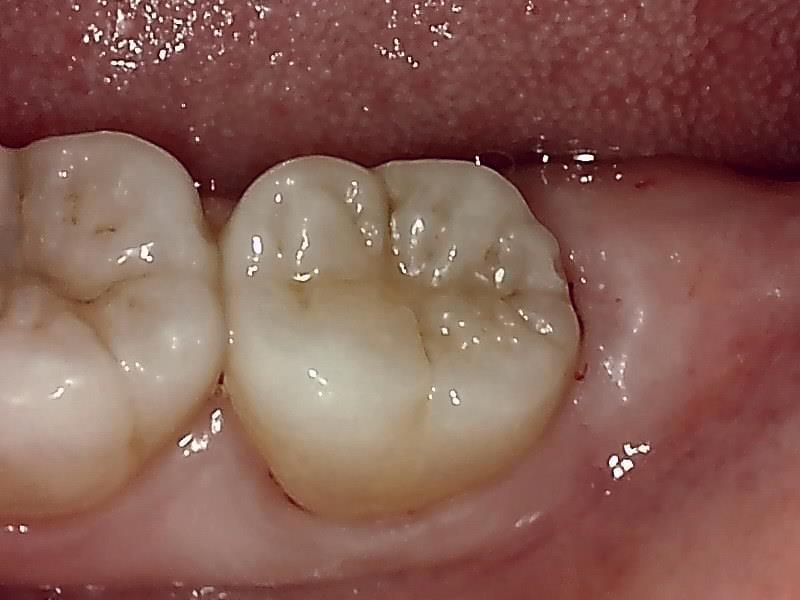

【Befor】

部位:左下8番埋伏歯